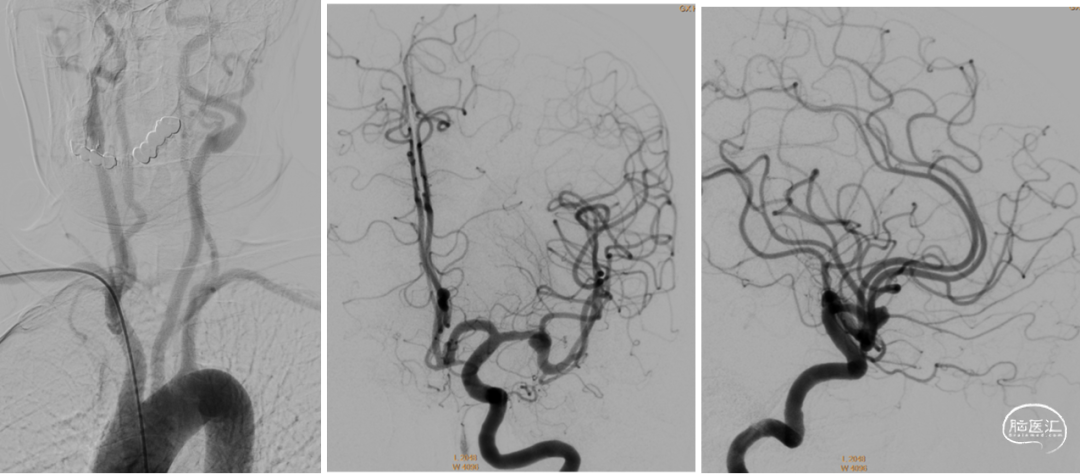

DSA

DSA

DSA